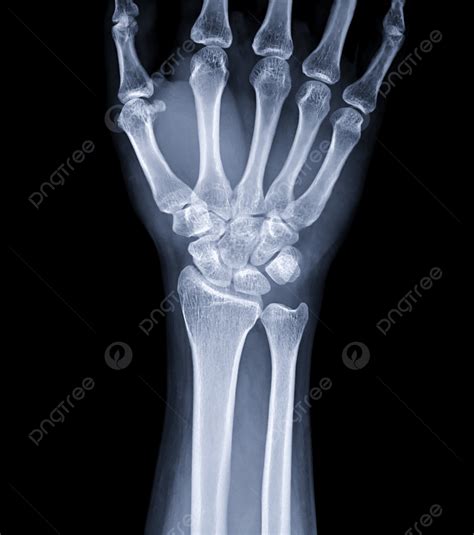

What to Expect During the Imaging Procedure

Getting an X Ray Normal Hand is a quick and painless process. You will typically be asked to place your hand flat on the image receptor. The technologist will likely capture the hand in a few different angles, most commonly the posteroanterior (PA), oblique, and lateral views. These multiple angles are crucial because a single view might hide a fracture that overlaps with another bone.

View Purpose

Posteroanterior (PA) Provides a standard overview of the carpal, metacarpal, and phalangeal bones.

Oblique Helps visualize the overlapping bones of the mid-hand and reduces superimposition.

Lateral Essential for assessing the alignment of the joints and identifying displaced fractures.

💡 Note: Remove all jewelry, such as rings or watches, from the hand and wrist area before the procedure to prevent artifacts from appearing on the final image.